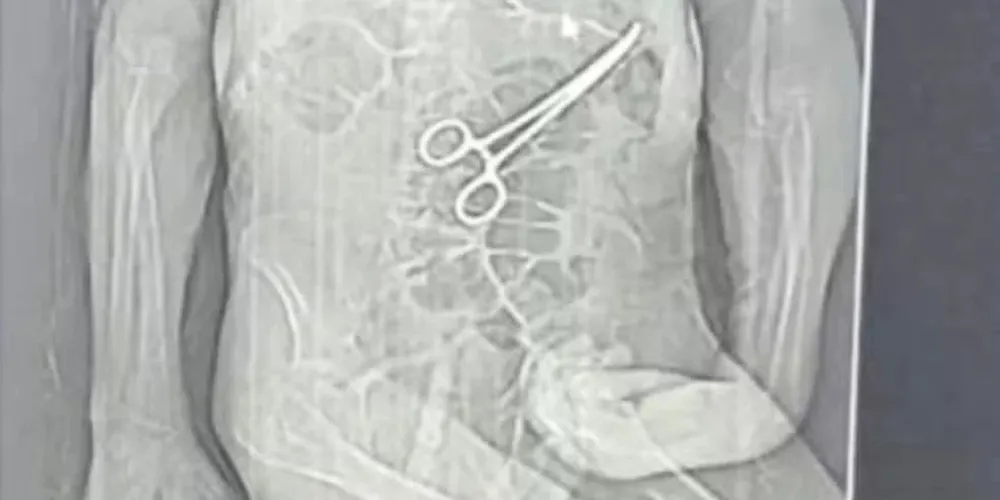

Após a morte, a família teve conhecimento de uma tomografia divulgada por uma rádio local que indicaria a presença de uma pinça cirúrgica dentro do corpo do paciente. Segundo o advogado dos familiares, Iuri Evangelista Furtado, a partir desse exame começaram a ser adotadas medidas legais.

Um homem, de 68 anos, morreu na véspera do Natal, após passar por duas cirurgias no Hospital Municipal de João Pinheiro, no noroeste de Minas Gerais. A família de Manoel Cardoso de Brito acusa a unidade de saúde de erro médico e afirma que uma pinça cirúrgica foi esquecida dentro do corpo do paciente após o primeiro procedimento.

A Secretaria Municipal de Saúde confirmou que houve a retirada de um corpo estranho durante a cirurgia e informou que abriu uma sindicância para apurar o caso.